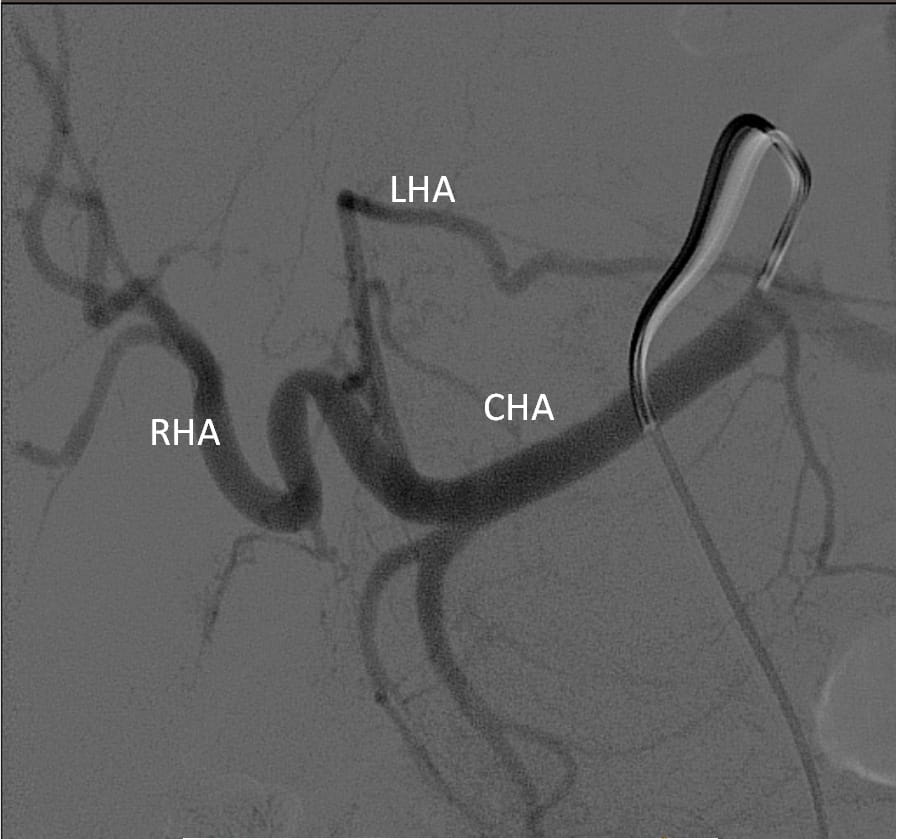

قام اليوم الفريق الطبى بقسم الأشعة التداخلية بمستشفيات جامعة بنها وبمساعدة لواء طبيب اسامه زين أستاذ الاشعة التداخليه بالاكاديمية الطبية العسكرية بإجراء عملية حقن ورم كبدي كبير الحجم لمريضة تبلغ من العمر 51 عاما وذلك بعد عمل اشعة مقطعية ورنين مغناطيسي لتحديد طبيعة الورم.

حيث تعد هذه العملية الاولى من نوعها التى يتم عملها من خلال جهاز الأشعة المقطعية ١٢٨ متعدد المقاطع حيث تم علاج الورم من خلال قسطرة بالشريان الكبدي للفص الأيسر من الكبد ونجاح عملية الحقن التي تظهر اختفاء الاوعيه الدمويه المغذيه للورم.